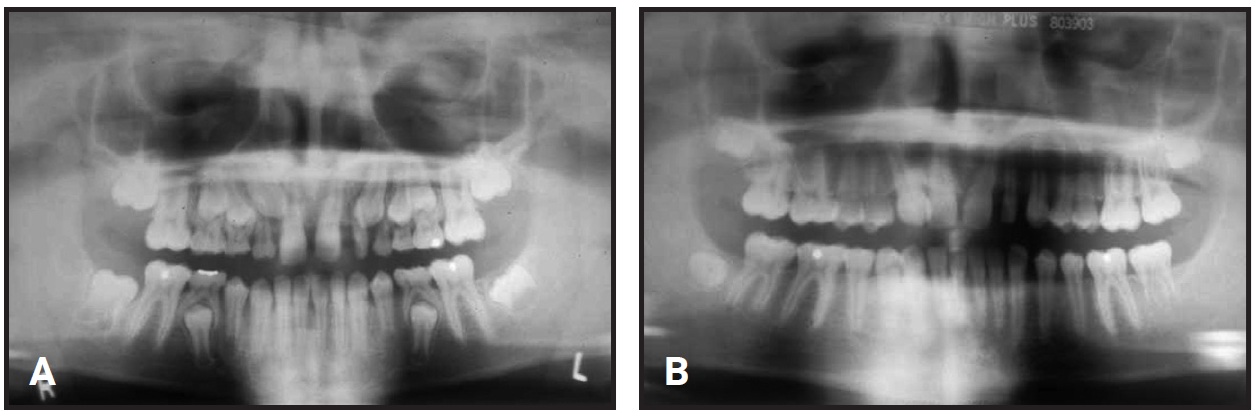

Fig. 6 Case 5. A. 11½-year-old patient with bilateral ectopic maxillary canines, missing maxillary right lateral incisor, and small left lateral incisor before extraction of maxillary deciduous canines. Late eruption for chronological age is common with ectopic teeth. B. One year later, positions of maxillary permanent canines improved after extraction of deciduous canines.

Extraction of the maxillary deciduous canines, maxillary expansion, and/or headgear treatment frequently improve the ectopic permanent canine positions and encourage normal eruption. Similarly, space opening improves the likelihood that the ectopic permanent canine will erupt without surgical intervention.9-11 When the tip of the maxillary canine has not crossed the midpoint of the lateral incisor, extraction of the deciduous canine alone results in an improved permanent canine position 91% of the time.12